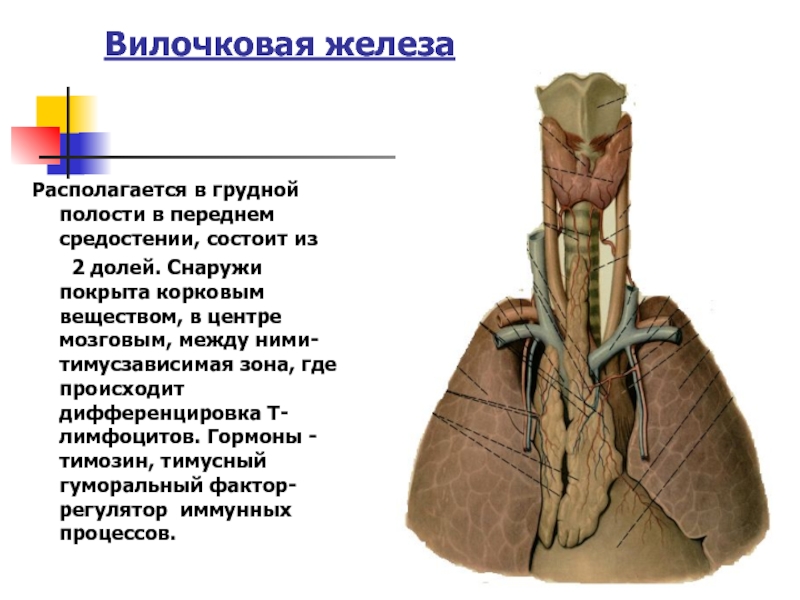

Фотографии вилочковой железы тимуса: структура и функции